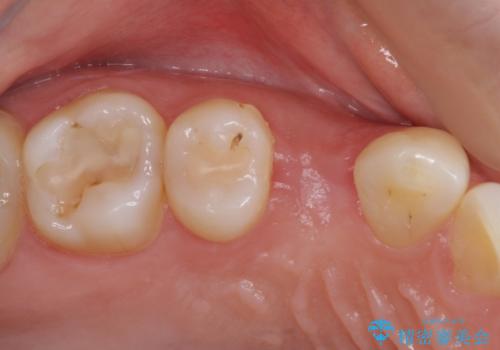

深い虫歯の歯を抜歯 目立つ小臼歯のインプラント治療

- 他院で抜歯が必要と診断され、インプラント治療を希望して来院された患者様です。

口を開けたときに目に付く領域であったので、ジルコニアカスタムアバットメントを用いたインプラント治療を行うこととしました。